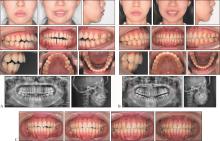

隐形矫治技术发展20多年,已从单纯的牙齿排齐工具发展为多学科口腔治疗的核心手段,尤其在牙周病正畸治疗、颞下颌关节紊乱病(TMD)正畸治疗、修复种植正畸联合治疗及正畸正颌联合治疗中展现显著优势。牙周病正畸治疗的目标是促进健康与稳定。建议牙周炎症控制后介入正畸治疗,实行轻力渐进原则,减少牙移动步距,减少隐形矫治器包裹,延长牙套替换时间。TMD正畸治疗的目标是咬合—关节协调,解除咬合创伤,稳定关节功能,排齐牙列,改善咬合。正畸介入时机仅适于稳定期TMD,强调多学科联合管理,患者正畸治疗的知情同意非常重要。修复种植正畸联合治疗的目标是空间与美学整合。隐形矫治的数字化设计可集中间隙,拓展修复种植空间,压低伸长对颌牙,直立倾斜的基牙,为修复种植提供理想的𬌗龈距离及近远中径,配合微笑设计等提升红白美学指数。严重骨性畸形的正畸正颌联合治疗可实现正畸—手术精准协同。隐形矫治数字化设计,上下牙弓宽度匹配相对固定矫治更容易实现,有效减少椅旁操作时间,提升矫治效率。目前隐形矫治在多学科领域里的应用还相对有限,高质量研究也不多,期待未来有更多高质量的研究以提高对隐形矫治的认识,让更多患者能精准高效地完成隐形矫治。

Clear aligner treatment has evolved over the last 20 years. It has transformed from a simple tool for tooth alignment to an essential component of multidisciplinary oral treatment. It has shown significant advantages in the orthodontic treatment of periodontal disease, the orthodontic treatment of temporomandibular joint disorder (TMD), integrated approaches with dental implant restoration, and the combined treatment of orthodontics and orthognathic surgery. The objective of orthodontic treatment for periodontal disease is to enhance health and stability. Commencement of clear aligner treatment is advised after the management of periodontal inflammation. The principle of applying gentle and gradual force must be adhered to. The extent of tooth movement should be reduced. The coverage of the aligner should be minimized. The time between aligner replacements should be extended. The objective of orthodontic treatment for TMD is to achieve occlusal-joint coordination, eliminate occlusal trauma, stabilize joint function, align the teeth, and improve occlusion. Clear aligner intervention is only suitable for stable TMD. Emphasis is placed on collaborative multidisciplinary management. Informed consent for orthodontic treatment of patients with TMD is crucial. The goal of combined orthodontic and restorative treatment is to integrate space and aesthetics. The digital design of clear aligners can optimize spacing, expand the area for dental implants, intrude over-erupted opposing teeth, upright tilted abutment teeth, ensure optimal gingival distance and mesiodistal diameter for dental implants, and when combined with smile design, it can significantly improve the pink and white aesthetic score. Precise orthodontic-surgical coordination is achieved for the combined treatment of severe skeletal malocclusion via orthodontics and orthognathic surgery. The digital design of clear aligners facilitates the alignment of the upper and lower dental arches more effectively compared with fixed orthodontic treatment. It effectively reduces chairside operation time and significantly improves treatment efficiency. At present, the application of clear aligners in multidisciplinary fields remains limited, and high-quality studies are lacking. We anticipate further high-quality research in the future to enhance our understanding of clear aligner treatment. This will facilitate the exact and rapid completion of clear aligner therapy for patients, resulting in aesthetically pleasing smiles.